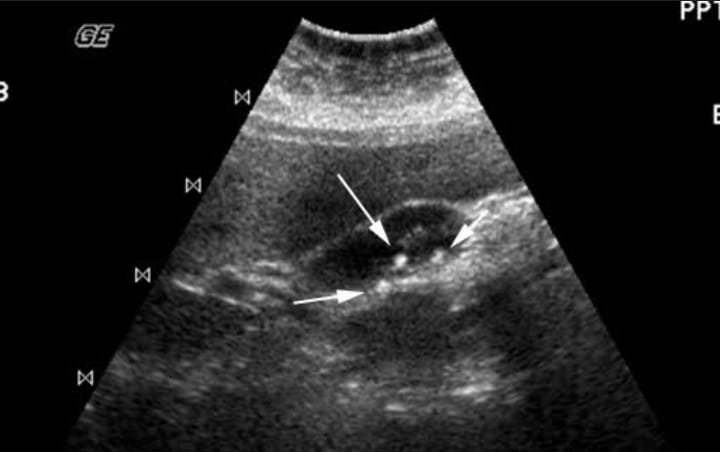

التهاب المرارة.. الاسباب والاعراض وطرق الوقاية

التهاب المرارة.. المرارة هي العضو المسؤول عن تخزين العصارة الصفراوية الاتية من الكبد، والتي تساعد في عملية الهضم بعد تفريغها فى الأمعاء الدقيقة عبر القناة الصفراوية الرئيسية، وفي معظم الحالات، تُسبب الحصوات الصفراوية التي تسد الأنبوب المؤدي إلى خارج المرارة الإصابة بالتهاب المرارة، ويؤدي ذلك إلى تراكم العصارة الصفراء التي يمكن أن تُسبب التهاب، وتشمل الأسباب الأخرى للإصابة بالتهاب المرارة وجود مشاكل في قناة المرارة أو أورام أو مرض خطيرة أو بعض أنواع العدوى.

التهاب المرارة